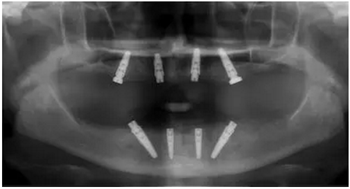

4枚NobelReplace CC RP4.3植體(11.5mm 軸向植體和13mm 傾斜植體)已植入完成:前牙區(qū)植體上裝配的是導(dǎo)板基臺(tái),后牙傾斜植體上裝配的是內(nèi)錐形連接的引導(dǎo)式持釘器。

使用內(nèi)錐形連接引導(dǎo)式持釘器在下頜前牙區(qū)植入NobelReplace CC植體。

4枚NobelReplace CC植體均已植入完成:前牙區(qū)植入NP 3.5*13mm植體并裝配引導(dǎo)式基臺(tái)以固定導(dǎo)板,后牙區(qū)植入RP4.3*16mm植體并裝配內(nèi)錐形連接引導(dǎo)式持釘器。